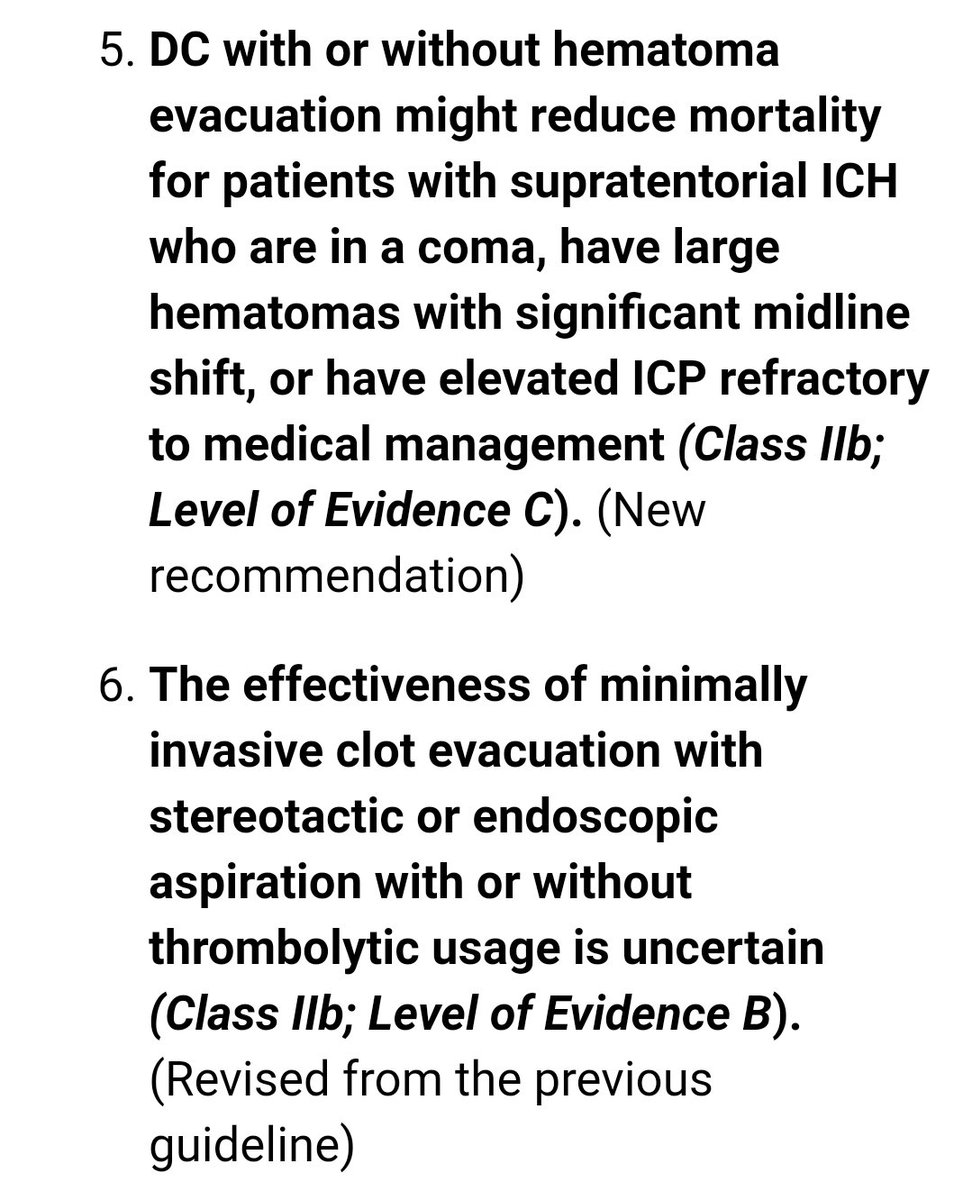

#السكته_الدماغيه_النزفيه

للاطباء🧠

Guidelines for the Management of Spontaneous Intracerebral Hemorrhage

للاطباء🧠

Guidelines for the Management of Spontaneous Intracerebral Hemorrhage